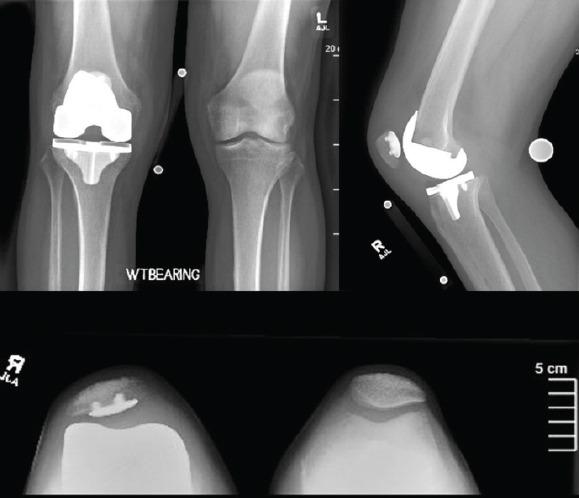

We present a case describing a novel technique in which the Mako robot (Stryker, Ft. Lauderdale, FL) was utilized for revision of a failed primary TKA secondary to aseptic loosening. The patient is a 68-year-old Caucasian male who underwent right revision TKA with robotic assistance. Stryker Triathlon TS implants were utilized with the use of both femoral and tibial cones and medial and lateral posterior femoral augments. He had satisfactory component alignment based on postoperative radiographs, and excellent clinical outcomes 6 months postoperatively.

我们介绍了一个病例,描述了一种新技术,即使用Mako机器人(史赛克公司,佛罗里达州劳德代尔堡)对因无菌性松动导致初次TKA失败的患者进行翻修。患者是一名68岁的白人男性,在机器人辅助下接受了右膝翻修TKA。使用了史赛克Triathlon TS植入物,包括股骨和胫骨锥体以及股骨内外侧后髁增大装置。根据术后X光片,假体排列满意,术后6个月临床效果良好。